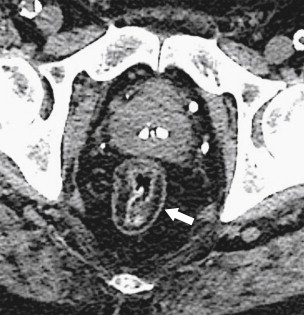

Ultrasound (US) sometimes shows a hypoechoic cystic mass with a thick wall, which has an echogenic outer layer and hypoechoic inner layer. On BE the cyst produces a mass effect of adjacent bowel and on CT appears as a nonenhancing mass, compressing or displacing the adjacent bowel, which may contain simple fluid, hemorrhage, or proteinaceous fluid ( Fig. 5-4 ). On MRI the enteric cysts are usually hyperintense on T2-weighted imaging, reflecting their cystic nature ( Fig. 5-5 ). Because many duplication cysts contain ectopic gastric mucosa, a Tc-99m pertechnetate radionuclide study can often show radionuclide uptake, which can also be observed within a Meckel diverticulum for the same reason.

Figure 5-4, Axial contrast-enhanced CT in a 46-year-old woman with a 4.5-cm homogeneous pararectal mass ( arrow ) caused by rectal enteric duplication.